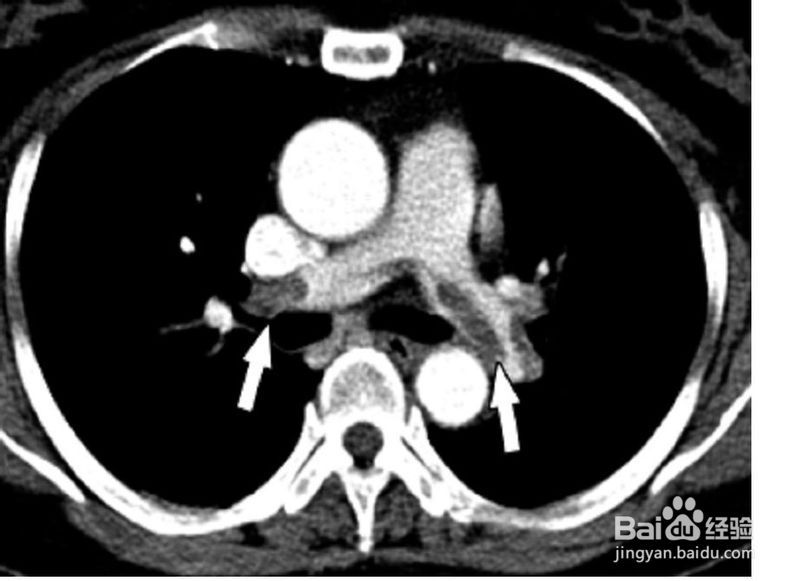

四大胸痛杀手